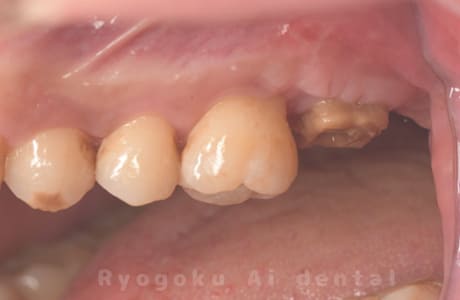

Case12

-

- 原因

- 縁下カリエス

- 治療内容

- クラウンレングスニング、ジルコニアクラウン修復

- 治療費用

- 約220,000円

被せ物の中から臭いがするとのことで、被せ物を外したところ大きな虫歯となっていました。このまま被せてしまうと被せ物が外れやすいため、埋まっている歯を出すためのクラウンレングスニング処置を行い、その後、ジルコニアクラウンで被せ物を行いました。